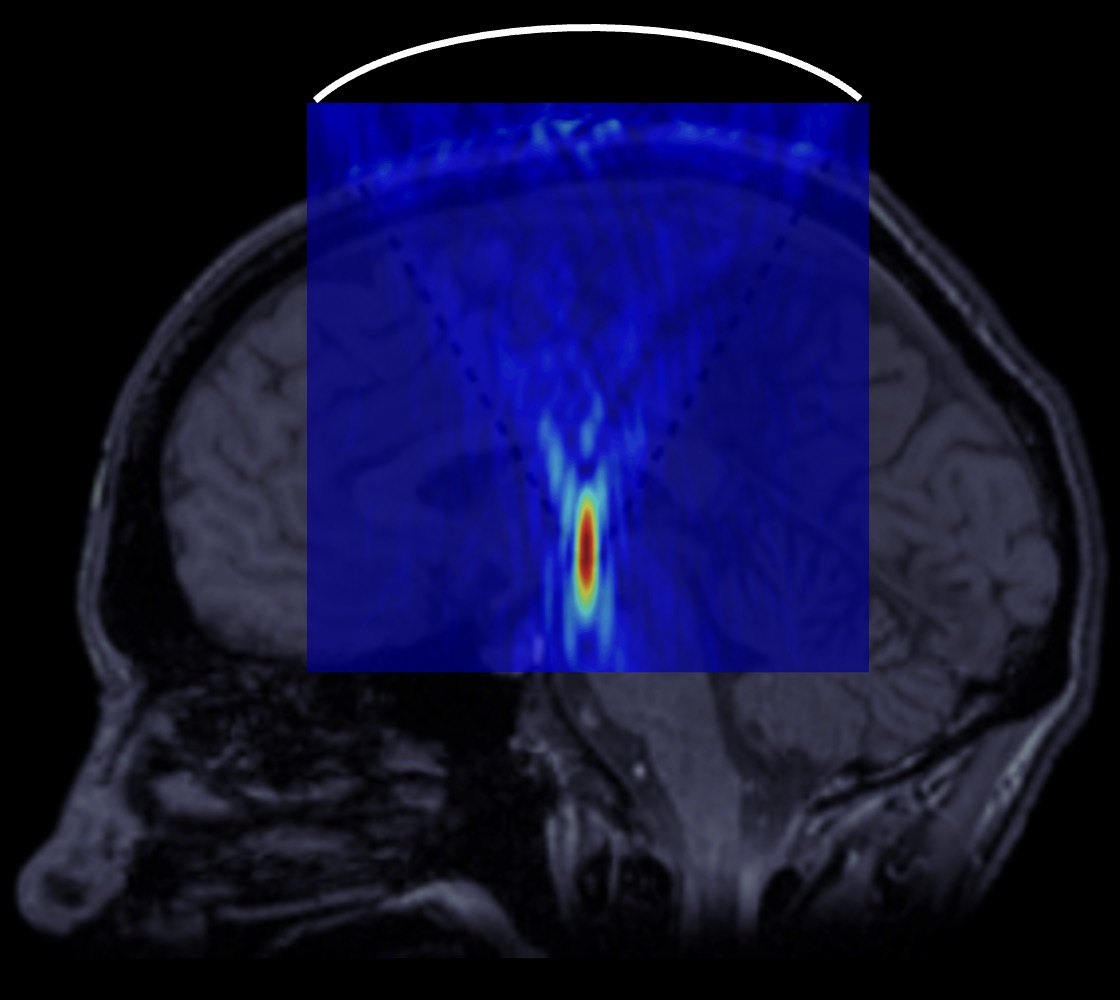

Активно развиваемые в последнее время методы неинвазивной хирургии с помощью высокоинтенсивного фокусированного ультразвука (HIFU – high-intensity focused ultrasound) обеспечивают возможность бесконтактного разрушения задаваемых участков головного мозга путем ультразвукового нагрева ткани до температур теплового некроза под контролем магнитно-резонансной (МР) термографии. Технология теплового HIFU используется в клиниках России и других стран для лечения двигательных расстройств (эссенциального тремора, тремора при болезни Паркинсона, дистонии и др.) путем создания локализованных тепловых разрушений внутри головного мозга. Однако на сегодняшний день достижимая область мозга для тепловой HIFU-хирургии ограничена центральными отделами головного мозга – таламусом и бледным шаром – из-за опасности перегрева эффективно поглощающих ультразвук костей черепа при неглубокой фокусировке. Также ограничивающими факторами являются диффузия тепла и кровотока, снижающие точность воздействия, и необходимость использования дорогостоящих аппаратов МР-томографии для контроля температуры во время операции.

Схема, иллюстрирующая проведение нейрохирургических операций с помощью высокоинтенсивного фокусированного ультразвука. Вне головы пациента располагается фокусирующий излучатель, направляющий акустический пучок в задаваемую область мозга.

В связи с этим, в наших недавних исследованиях совместно с Университетской клиникой МНОИ МГУ, НИИ пульмонологии и НИИ морфологии человека были проведены первые эксперименты, демонстрирующие принципиальную возможность получения механических разрушений в различных тканях головного мозга человека для начала, ex vivo (т.е. вне организма) и в отсутствие черепа. Также удалось получить механические разрушения в таламусе и бледном шаре – тех отделах мозга, которые в современной клинической практике подвергаются тепловому HIFU-разрушению для лечения двигательных расстройств под контролем МРТ.